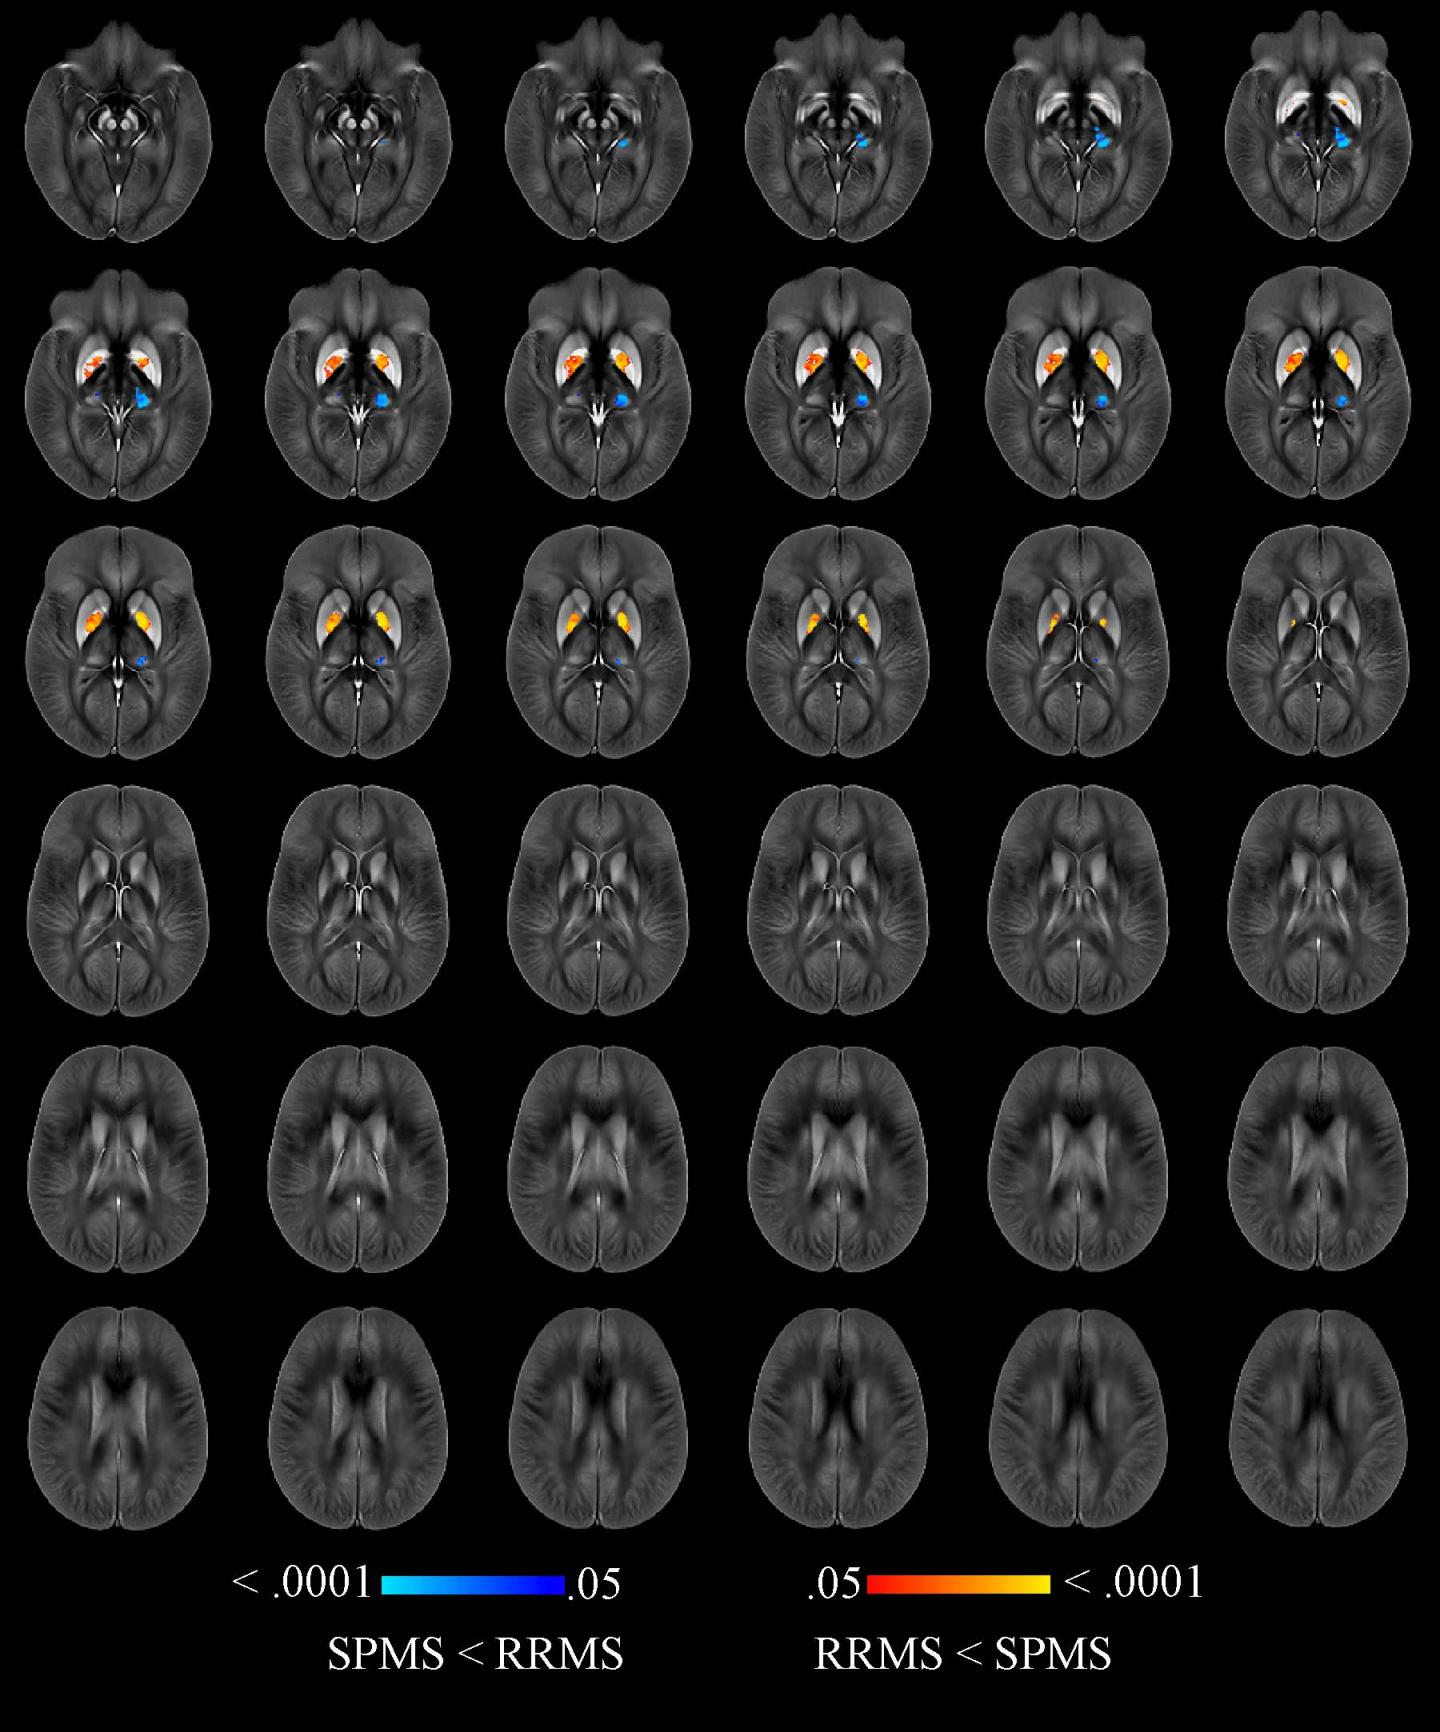

Dr. Zivadinov and colleagues recently compared brain iron levels in people with MS to those of a healthy control group using an advanced MRI technique called quantitative susceptibility mapping. A brain region with more iron would have higher magnetic susceptibility, and one with less iron would have lower susceptibility.

The researchers performed the mapping technique on 600 MS patients, including 452 with early-stage disease and 148 whose disease had progressed.

Compared to 250 healthy control participants, MS patients had higher levels of iron in the basal ganglia, a group of structures deep in the brain that are central to movement. However, the MS patients had lower levels of iron in their thalamus, an important brain region that helps process sensory input by acting as a relay between certain brain structures and the spinal cord. The lower iron content in the thalamus and higher iron content in other deep gray matter structures of people with MS were associated with longer disease duration, higher disability degree and disease progression.

This association with clinical disability persisted even after adjusting for changes in the brain volumes of each individual structure.

"In this large cohort of MS patients and healthy controls, we have reported, for the first time, iron increasing in the basal ganglia but decreasing in thalamic structures," Dr. Zivadinov said. "Iron depletion or increase in several structures of the brain is an independent predictor of disability related to MS."